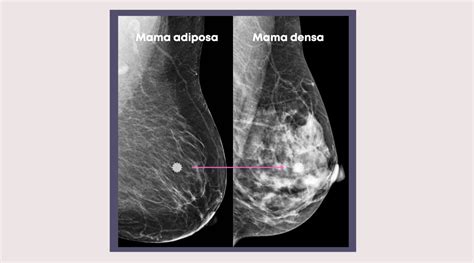

- Mamografía: Puede detectar zonas densas, quistes y nódulos. Los nódulos con contornos bien definidos suelen ser indicativos de benignidad.

- Ecografía: Es considerada el método diagnóstico de elección en la mastopatía fibroquística. Permite diferenciar con alta precisión si una lesión es quística o sólida, y caracterizar su contenido. Puede mostrar imágenes similares a las de tumores quísticos, pero diferenciándose en número y diámetro.

Mamografía vs Ecografía mamaria